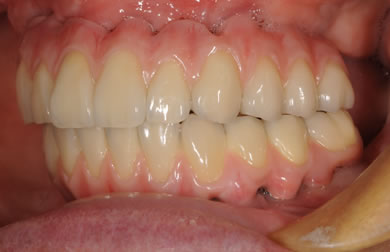

インプラントの症例写真 IMPLANT

骨再生スピードインプラント治療+AGC連結セラミック治療

| 性別/年齢 | 女性 / 57歳 | ||||||||||||||||||||||||||||||||

| 主訴 | 全体的に歯が無いので相談したい。 | ||||||||||||||||||||||||||||||||

| 治療方針 | 骨再生療法にて骨量を回復するとともに軟組織も移植し、機能的回復だけでなく審美的回復も行う。 | ||||||||||||||||||||||||||||||||

| 治療内容 | インプラント12本(サイナスリフト+GBR+抜歯即日スピードインプラント+遊離歯肉移植)、AGCハイブリッドセラミック連結ブリッジ2装置(上顎・下顎)、テンポラリーインプラント2本 | ||||||||||||||||||||||||||||||||

| 総治療費 | 6,019,650円 | ||||||||||||||||||||||||||||||||

| 治療期間 | 1年0ヶ月 |